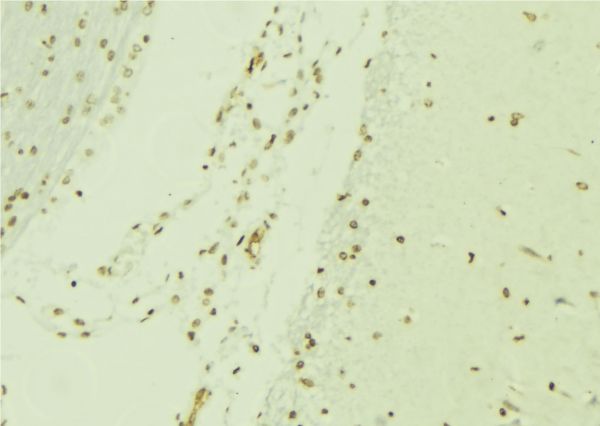

IHC (Immunohistochemistry)

(Immunochemical staining of human MAPK9 in human pancreas with rabbit polyclonal antibody (1:1000, formalin-fixed paraffin embedded sections).)